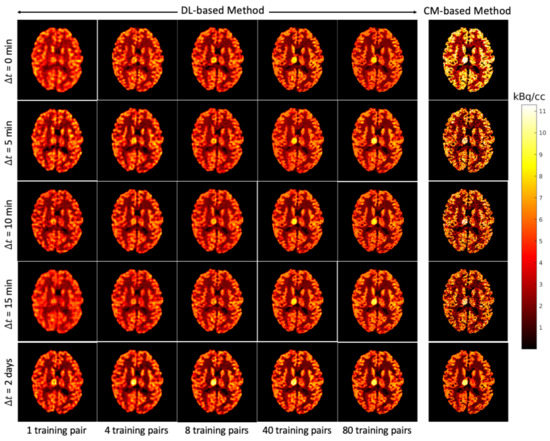

4.5. Bias and Standard Deviation Analysis (ROI-Level)

Finally, a comparison between the proposed DL-based method (with 3 training reruns, 80 training pairs) and the CM-based method (10 reruns with different random initial values of the kinetic parameters) was conducted for at the ROI level. To investigate the impact of the noise for the CM-based method at the ROI level, a full width at half maximum (FWHM) Gaussian kernel was used to denoise the separated images as a post-processing step. Figure 13 shows that the average of the CM-based separation results were sufficiently reduced by introducing an FWHM kernel after separation, and lower average bias was obtained for longer for the CM-based method with post-denoising. However, using a large FWHM kernel (8 mm) leads to higher average bias. The average of the DL-based method stays at a similar level for all , showing as the aleatoric uncertainty. For both [F]FDG and [C]MET, the average of the DL-based method is comparable to the CM-based method with a 4 mm FWHM kernel for different , which again indicates the DL-based method implicitly denoises the separated images as discussed in Section 4.1. For simultaneous injection ( = 0 min), the DL-based method overall delivers better separations at the ROI level than the CM-based method (with and without post-denoising) in terms of lower average and average . However, the CM-based method can still potentially surpass the DL-based method for at the ROI level by introducing an FWHM kernel (2–4 mm) as post-denoising for 5 min.

Figure 13.

Brain phantom (tumour ROI): average and average at the ROI level of separated static FDG images (a) and MET images (b) using DL-based and CM-based methods for the tumour ROI .